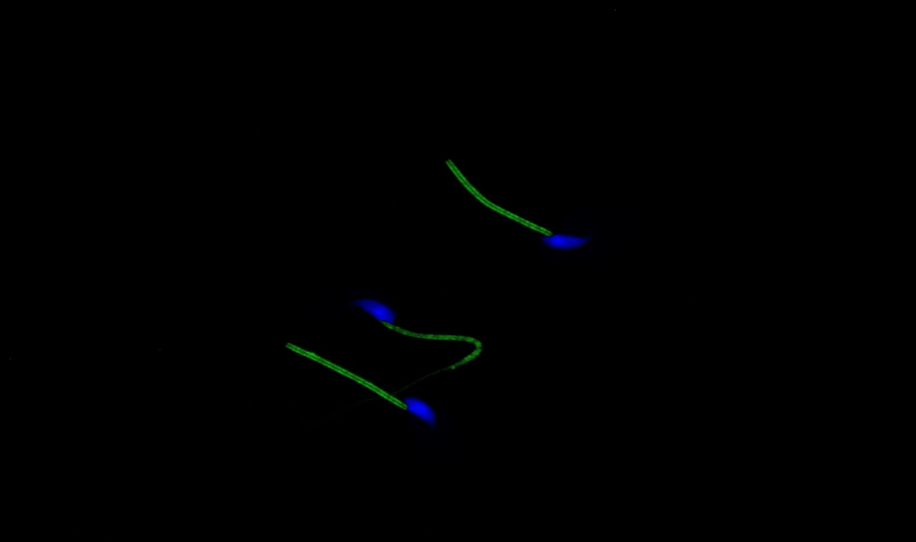

Mikroskopický snímek myších spermií, na kterých je zeleně zobrazeno sirovodíkové brnění.

„My jsme chtěli vědět proč. A proč pomáhá přidat zrovna sulfan. V té době se nevědělo, že spermie si sulfan samy produkují a co víc, že sulfan modifikuje, takzvaně persulfiduje, jejich proteiny a tím je chrání.“ Než se totiž spermie dostane k vajíčku, musí urazit dlouhou pouť samičím pohlavním traktem. Na této cestě tráví i několik dní, a přitom čelí mnoha nepříznivým vlivům včetně působení silně reaktivních volných radikálů. Ty se nacházejí v okolním prostředí, ale vznikají i v samotné spermii jako zplodiny intenzivního metabolismu při produkci energie potřebné k jejímu pohybu. Volné radikály mohou vážně poškodit bílkovinné molekuly a narušit životně důležité pochody ve spermii a tím tak i její schopnost oplodnit vajíčko.

„Proto si spermie vyrábí sulfan, který se váže na specifická ‚zranitelná‘ místa bílkovin ve spermiích a tím je chrání před poškozením. Tuto ochranu, jakési brnění, spermie získávají již během vývoje ve varleti. Na cestu pohlavním traktem samice tak vstupují náležitě vybaveny,“ přirovnává Hedvika Řimnáčová, která na výzkumu pracovala v rámci programu Cotutelle – doktorátu pod dvojím vedením. Roli sulfanu na mužskou plodnost zkoumala pod vedením Jana Nevorala a přední španělské odbornice Olgy García-Álvarez z Universidad de Castilla-La Mancha.